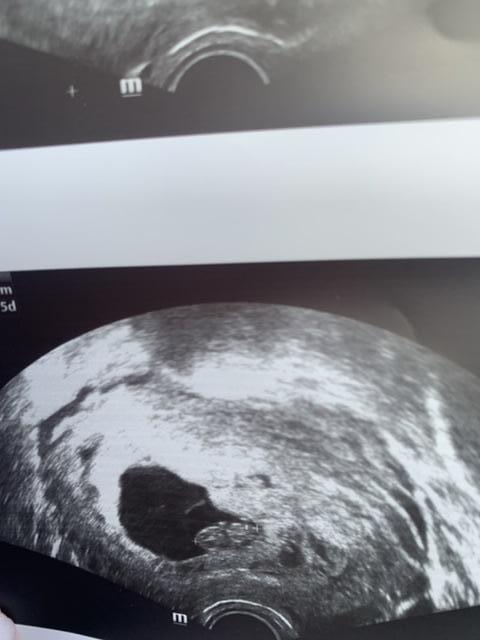

Метод Рамзи Узнали пол малыша❤️

А я думаю мальчик. Там вроде бы не по расположению малыша смотреть нужно, а по хориону, вроде как белым подсвечивает

До 8 недели смотрят, дальше неинформативно

Девочка(у меня так было,только сверху малышка была по узи,но тоже справа) Хотя по Рамзи не всегда совпадает

Мальчик. Но у мепя этот метод не сработал. По Рамзи девочка, а по факту мальчик)